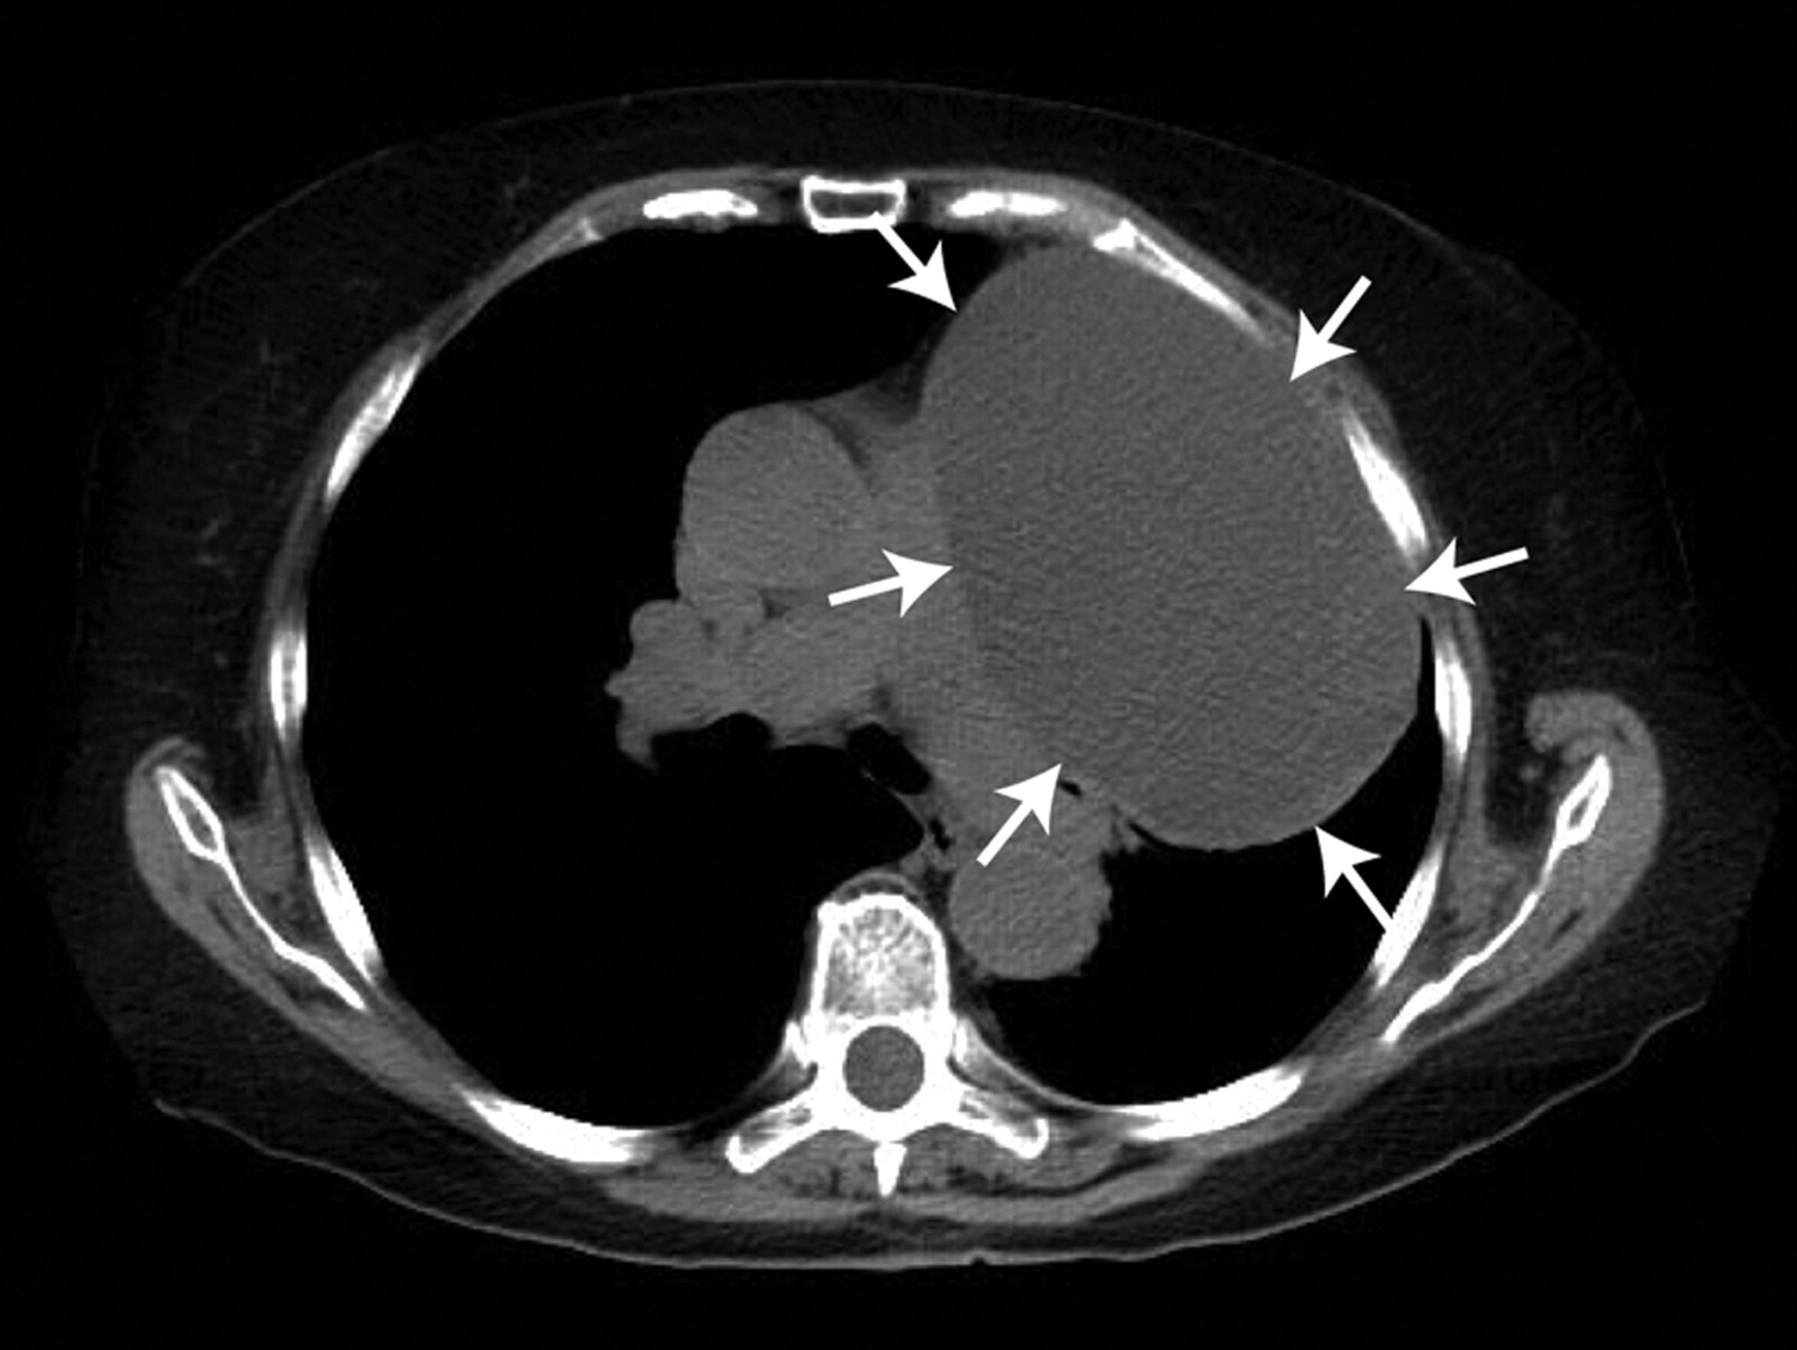

Case!

Code Stemi

• Cath: Non-obstructive CAD

• Admitted to CCU

• High O2 Requirements

• Please do echo for HF

Conclusion

• History of laryngeal SCC

• CT also shows pulmonary nodules

• Biopsy pending to confirm diagnosis

• Likely Metastatic SCC